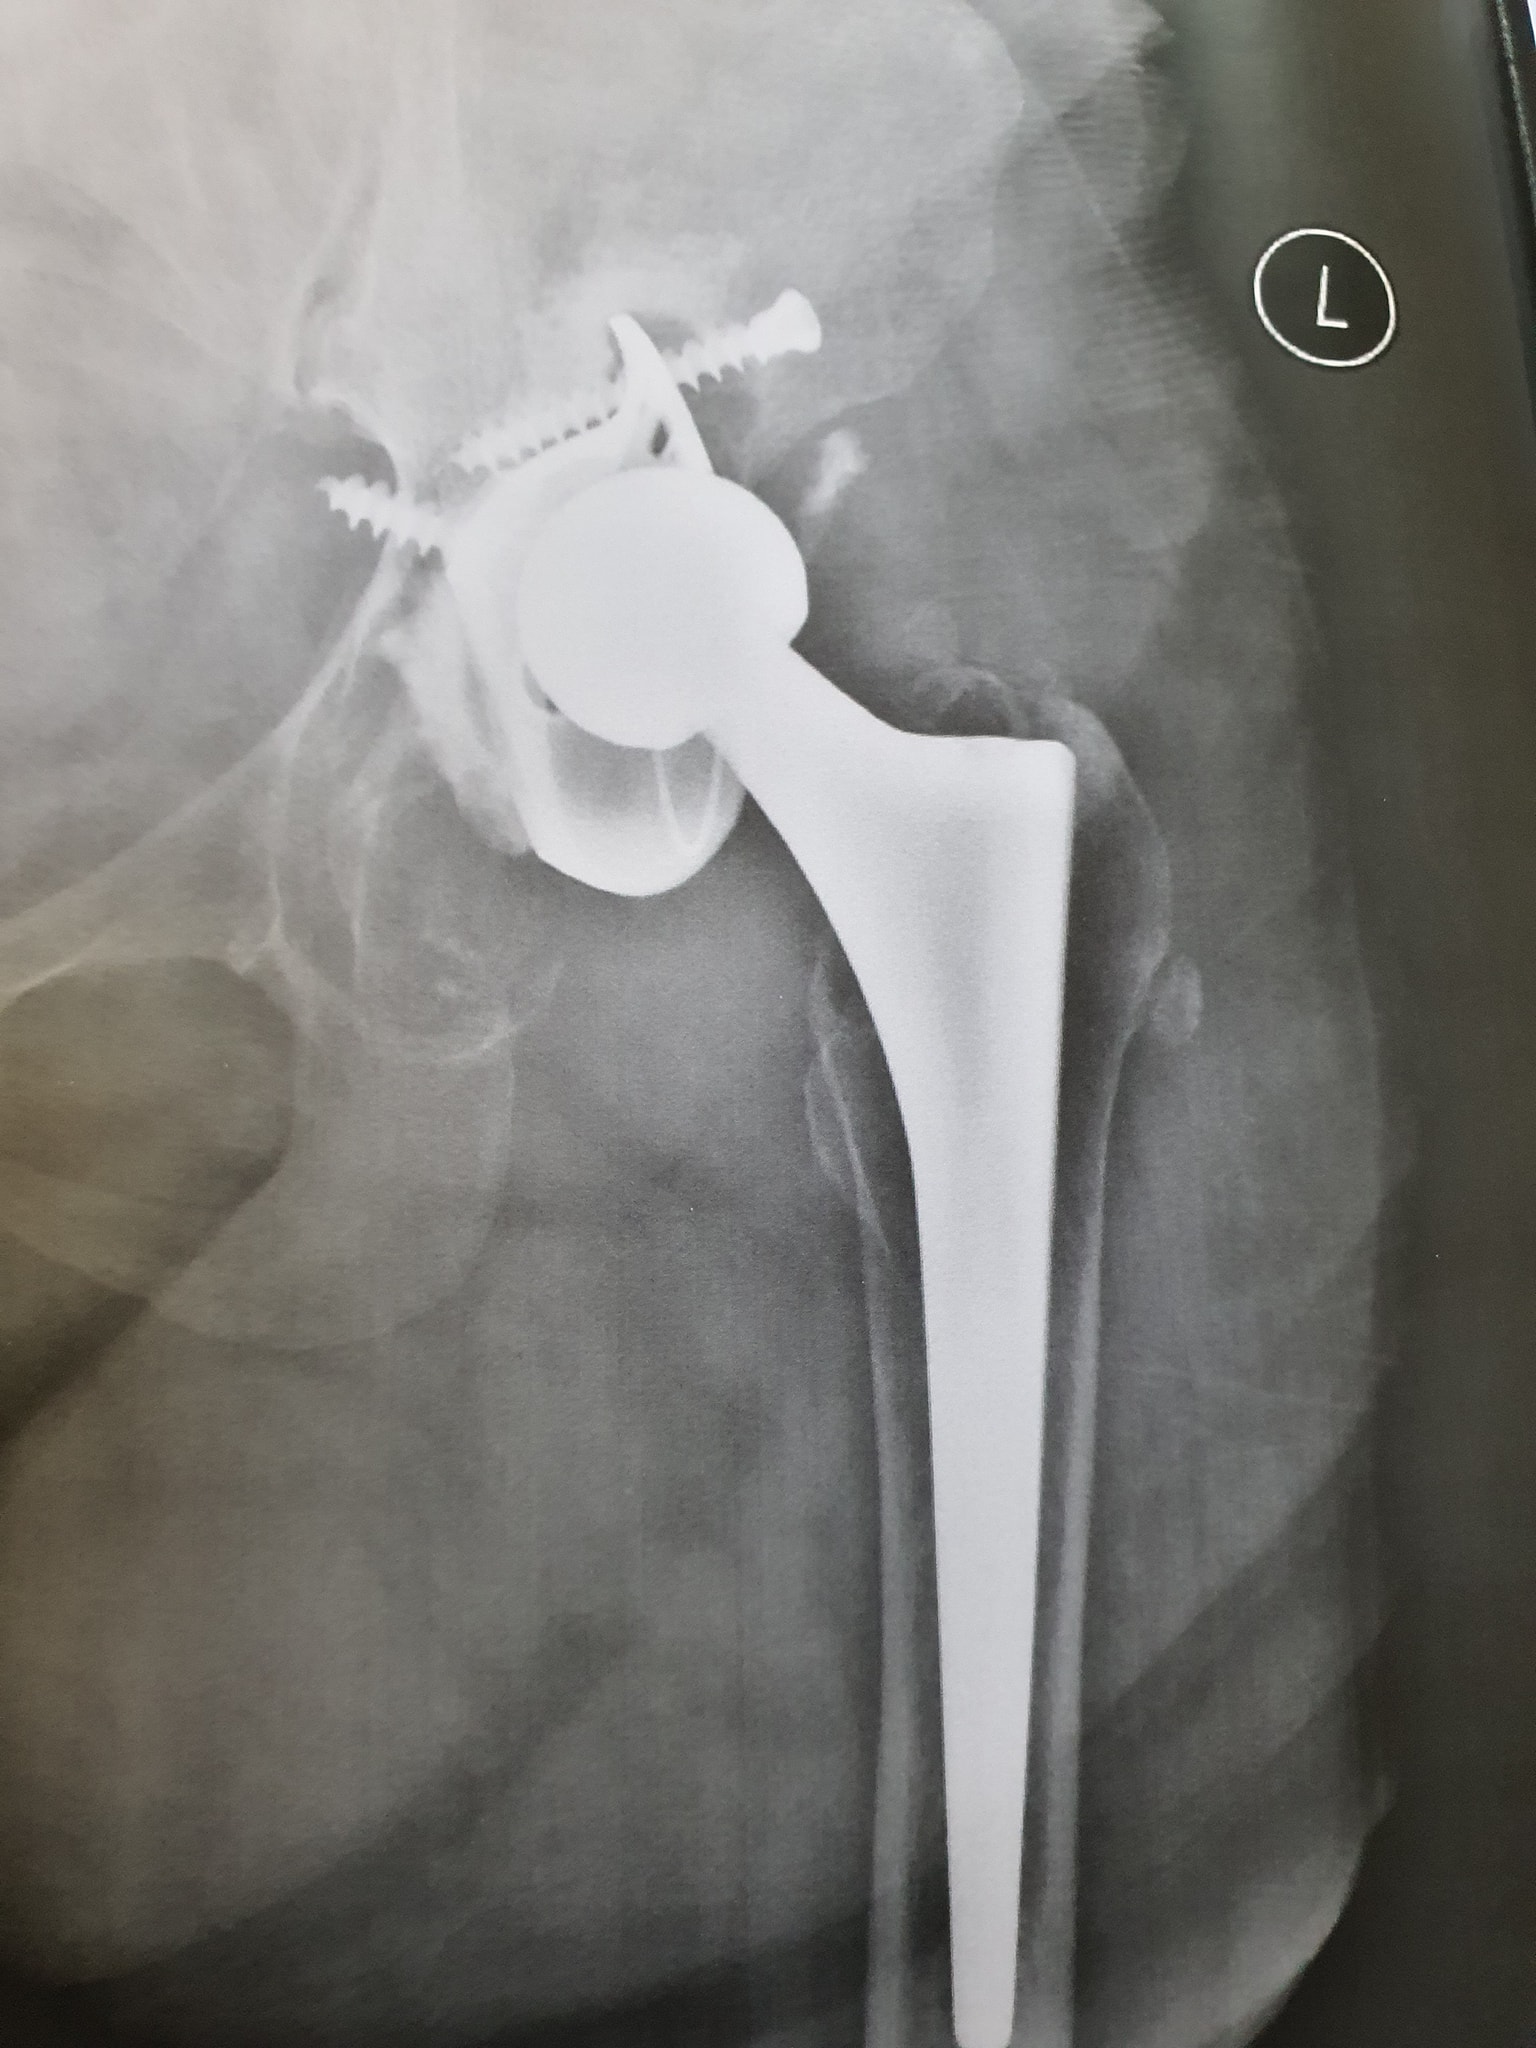

زراعة المفاصل الصناعية ورك و